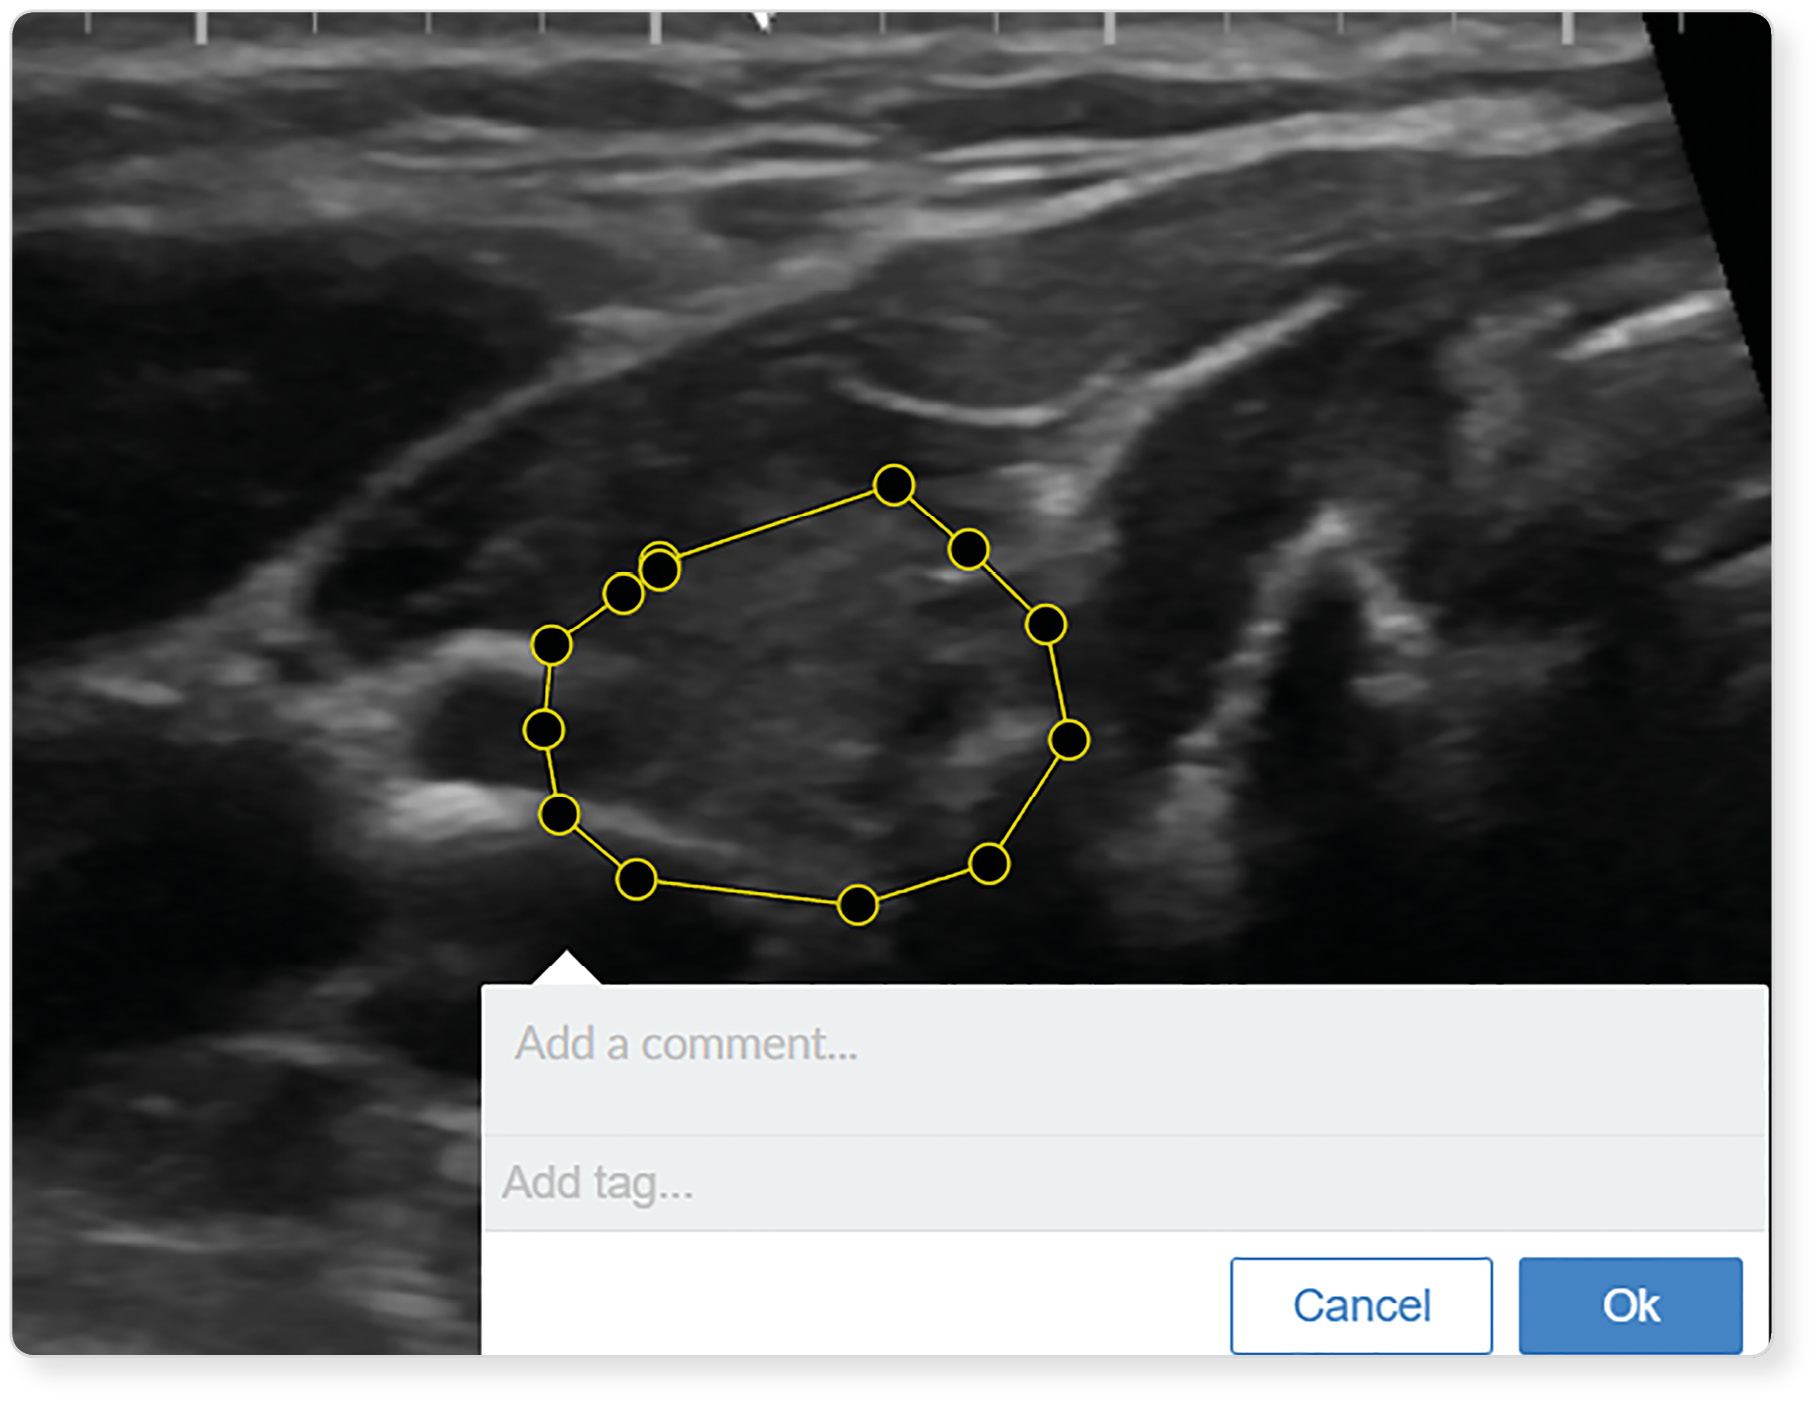

|  | 16. Рисунок 16. Изменение выделенных границ узлового образования. | |

| Тема | ||

| Тип | Исследовательские инструменты | |

|

Посмотреть

(296KB)

| Метаданные ▾ | |